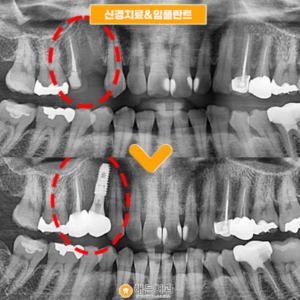

배방역치과 자연치아를 살리기 위해서는

배방역치과 자연치아를 살리기 위해서는 (치료기간 : 2022.03~2022.06) 안녕하세요. 오늘은 저희 배방역치과를 내원하여 임플란트와 치관확장술을 통해 크라운치료하신 환자분을 소개해 드릴까 하는데요. 아래 사진을 보면서 설명해 드리도록 하겠습니다. 배방역치과 위…